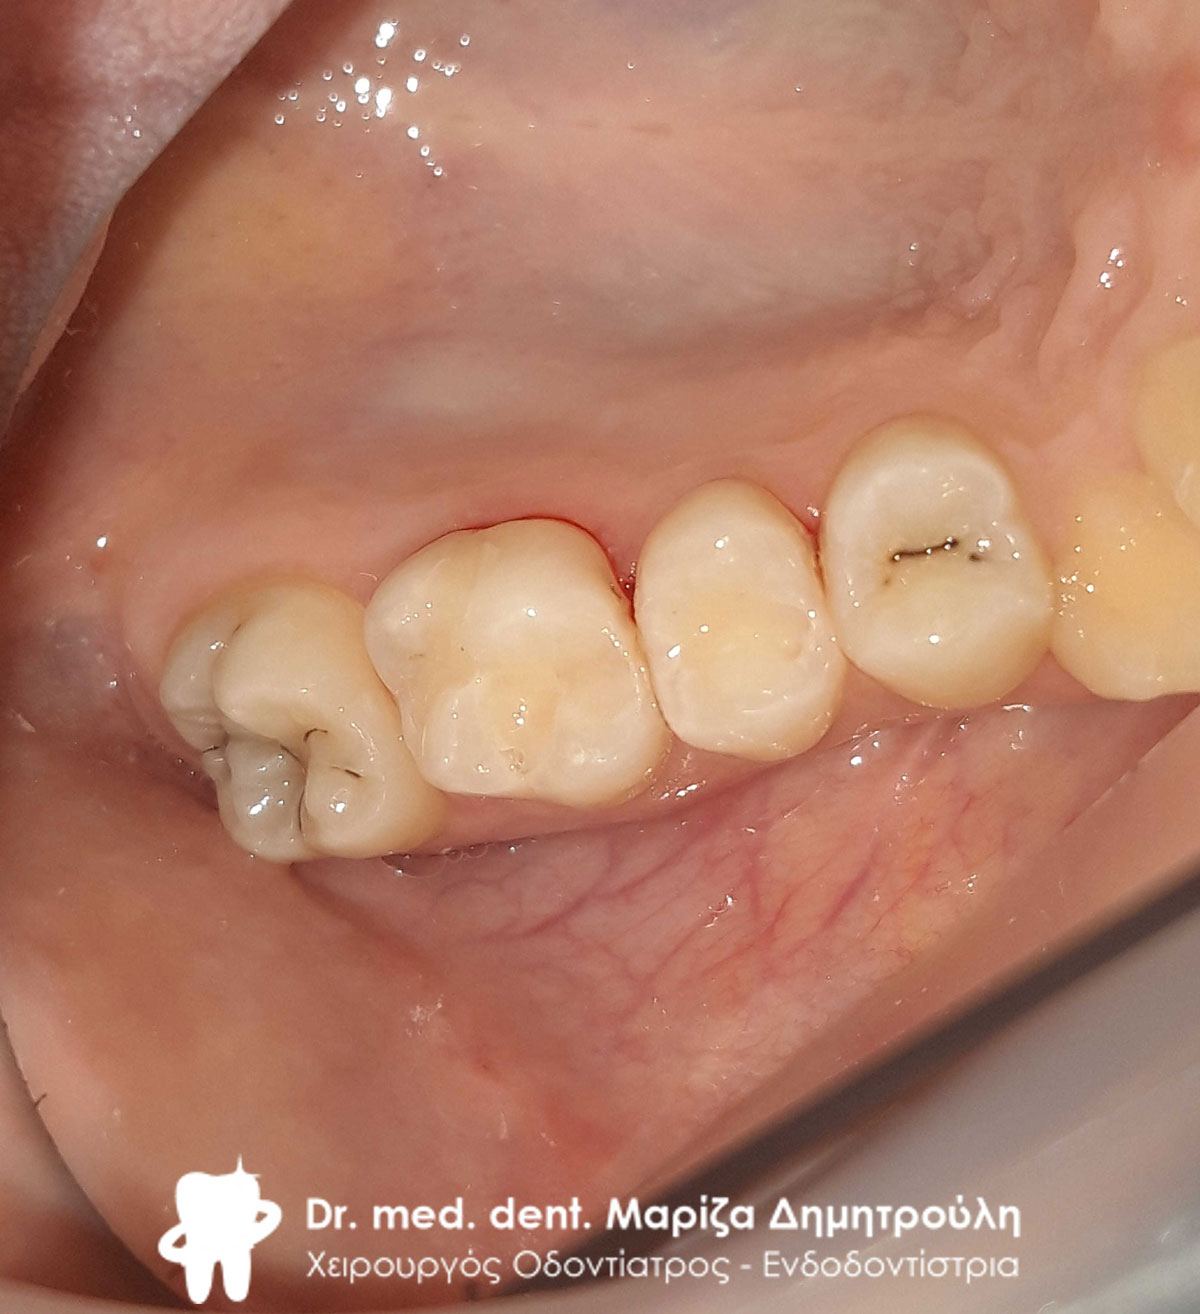

Αρχική κλινική εικόνα της δεξιάς πλευράς της κάτω γνάθου